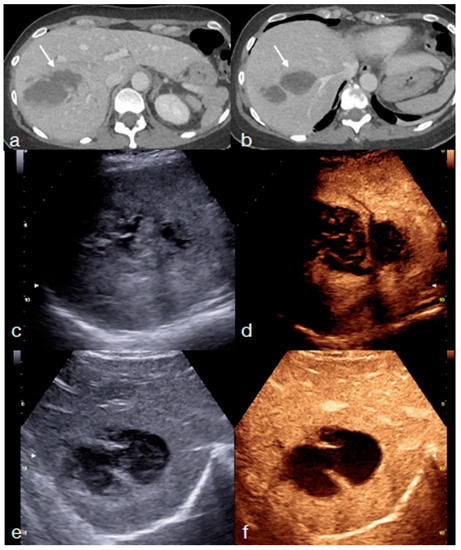

- Di Serafino, M.; Iacobellis, F.; Schillirò, M.L.; Ronza, R.; Verde, F.; Grimaldi, D.; Dell’Aversano Orabona, G.; Caruso, M.; Sabatino, V.; Rinaldo, C.; et al. The Technique and Advantages of Contrast-Enhanced Ultrasound in the Diagnosis and Follow-Up of Traumatic Abdomen Solid Organ Injuries. Diagnostics 2022, 12, 435. [Google Scholar] [CrossRef] [PubMed]

- Trinci, M.; Cirimele, V.; Ferrari, R.; Ianniello, S.; Galluzzo, M.; Miele, V. Diagnostic value of contrast-enhanced ultrasound (CEUS) and comparison with color Doppler ultrasound and magnetic resonance in a case of scrotal trauma. J. Ultrasound 2019, 23, 189–194. [Google Scholar] [CrossRef] [PubMed]

- Miele, V.; Piccolo, C.L.; Sessa, B.; Trinci, M.; Galluzzo, M. Comparison between MRI and CEUS in the follow-up of patients with blunt abdominal trauma managed conservatively. Radiol. Med. 2015, 121, 27–37. [Google Scholar] [CrossRef] [PubMed]